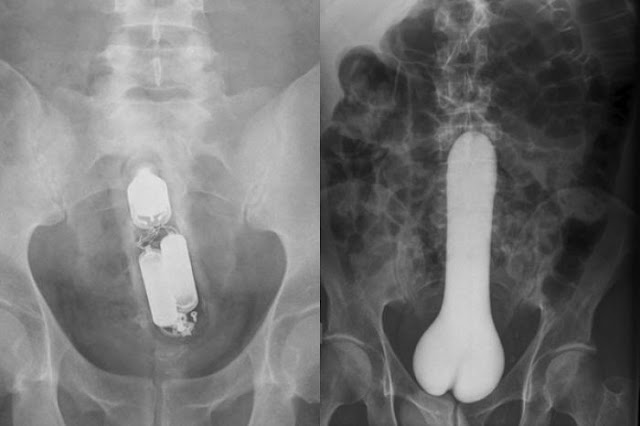

ภาพเอ็กซเรย์ ทำให้หมอรู้ว่าคนไข้เหล่านี้ไปทำอะไรกันมา..งานนี้มีอายหนักมาก 10:02 PM กดถูกใจ (Like) ติดตามข่าวสารจาก อรุณสวัสดิ์ Share Twitter Facebook Google Tumblr Pinterest Artikel Menarik Lainnya